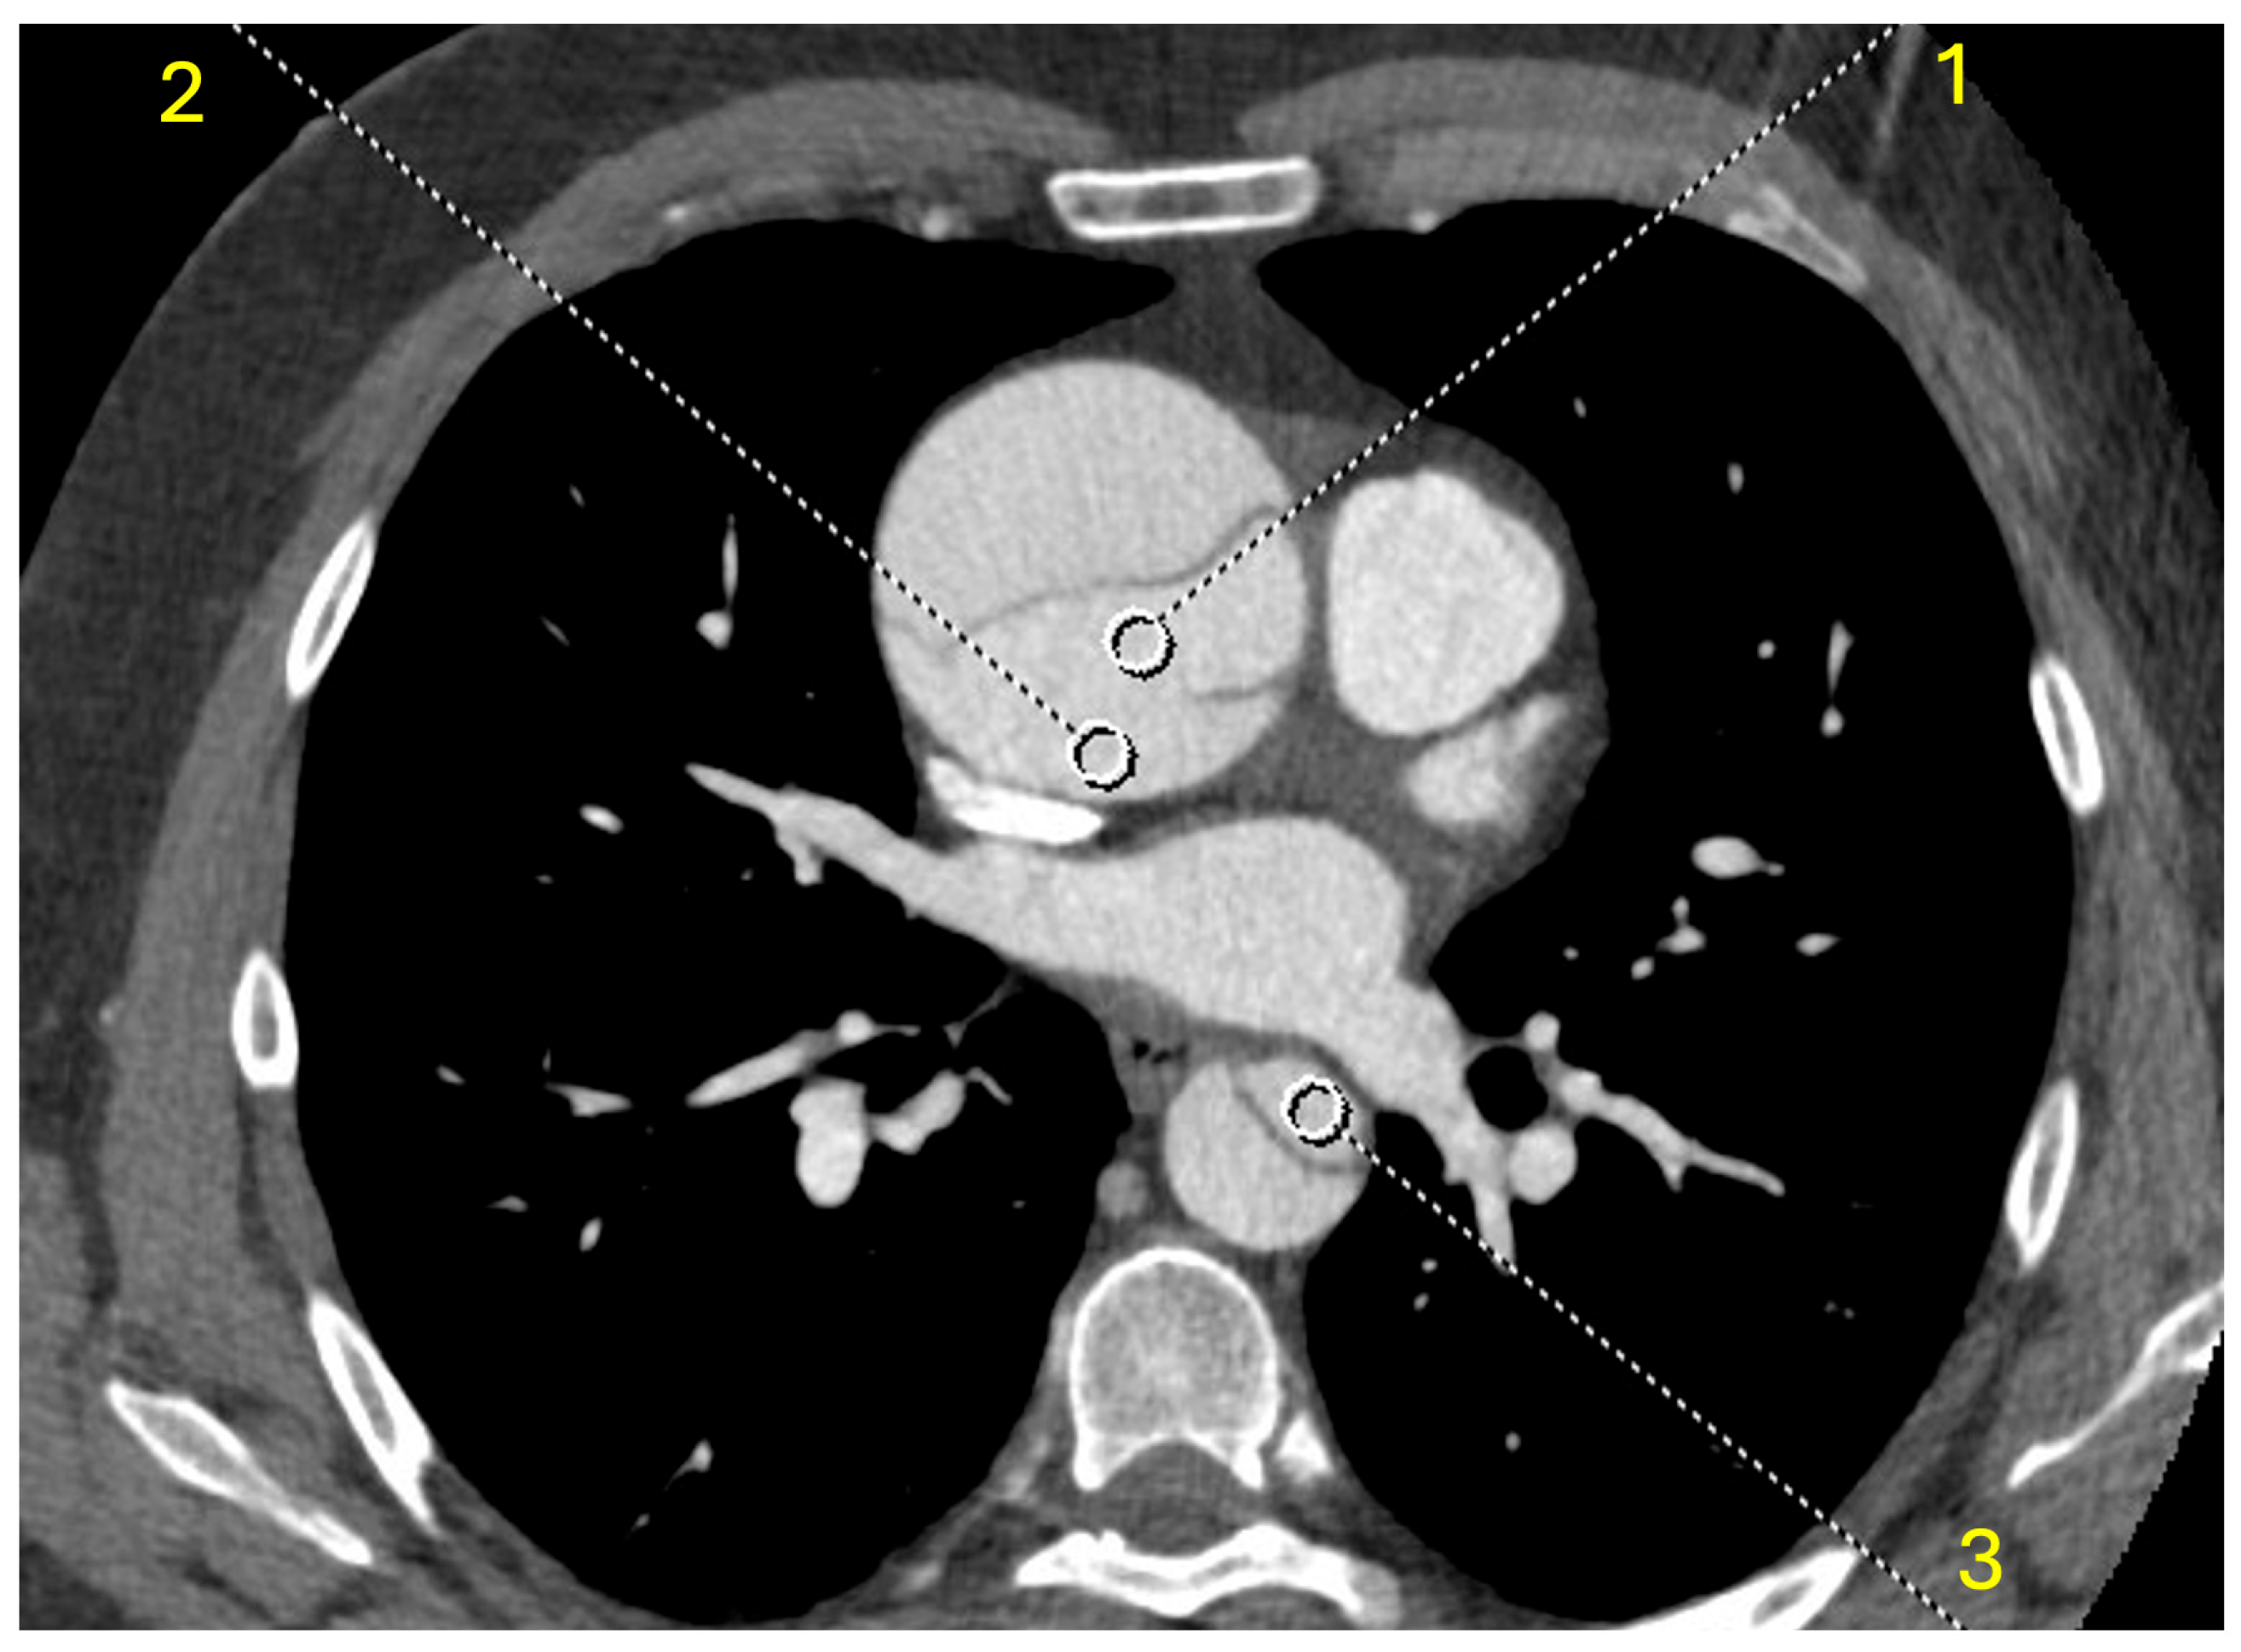

| 40 keV | 922 [780; 1127] | 997 [838; 1192] | 940 [841; 1116] | 810 [674; 1015] |

| 50 keV | 626 [536; 759] | 674 [574; 802] | 639 [572; 754] | 552 [466; 686] |

| 60 keV | 445 [390; 536] | 478 [412; 565] | 457 [406; 536] | 394 [334; 486] |

| 70 keV | 332 [297; 401] | 357 [310; 419] | 346 [305; 401] | 298 [248; 363] |

| 80 keV | 261 [239; 313] | 279 [246; 326] | 273 [242; 314] | 240 [197; 285] |

| 90 keV | 215 [196; 254] | 227 [204; 264] | 224 [201; 255] | 196 [162; 230] |

| 100 keV | 184 [167; 212] | 191 [174; 220] | 191 [172; 214] | 168 [138; 192] |

| 110 keV | 162 [145; 184] | 167 [154; 190] | 167 [151; 186] | 145 [121; 166] |

| 120 keV | 146 [131; 163] | 152 [137; 170] | 149 [136; 165] | 131 [111; 148] |

| 130 keV | 133 [120; 147] | 138 [126; 155] | 136 [124; 149] | 121 [100; 137] |

| 140 keV | 123 [112; 135] | 127 [117; 143] | 126 [116; 137] | 113 [94; 127] |

| 150 keV | 116 [105; 126] | 120 [110; 133] | 119 [108; 128] | 105 [89; 119] |

| 160 keV | 110 [99; 113] | 113 [105; 124] | 112 [103; 121] | 99 [85; 112] |

| 170 keV | 105 [95; 113] | 108 [99; 118] | 108 [99; 115] | 95 [82; 106] |

| 180 keV | 100 [92; 109] | 103 [96; 114] | 104 [95; 110] | 91 [79; 102] |

| 190 keV | 97 [89; 105] | 100 [93; 109] | 101 [92; 107] | 89 [77; 99] |

| VNC | 66 [57; 73] | 66 [59; 74] | 68 [63; 73] | 61 [49; 71] |

| NC | 48 [42; 55] | 46 [42; 55] | 50 [45; 57] | 44 [39; 55] |